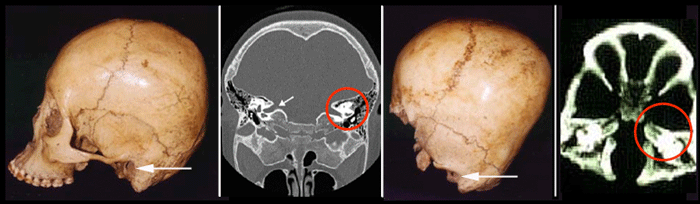

The human skull is made of plates that are separated by cracks or sutures. These sutures allow the skull to expand as the brain grows. They only fuse during later adult life. Infants and children suffering from hydrocephalus [above, left] typically have a round -- almost spherical -- shaped skulls as the fluid easily separates and expands the sutures.

The Starchild skull is slightly heart shaped. The skull expands on both sides of the saggital (center) suture. Examination of this suture shows that it is not fused and so could not restrict the expansion if it were caused by a build up of cerebral spinal fluid. This suggests that the shape of the skull was not caused by spinal fluid.

Another problem with attributing these deformities to hydrocephalus is the eye sockets. Hydrocephalus does not usually distort the shape of the eyes or bony orbits. Indeed children with this disorder have normal looking faces (see image above).

But the Starchild's eyes are extremely unusual.

Normal human eye sockets are 2" deep

and cone-like, with the optic nerve and

the foramen openings (holes for nerves connecting the eyes to the brain) at the farthest

point inside. The Starchild's sockets

are 0.7" deep, and the optic nerves and

foramens are located further down and closer

to the inner base of the nose. The surfaces of the Starchild's eye sockets

appear perfectly smooth. No shifts in their

terrain are evident to human eyes. Yet very

subtle shifts are there, and they are exactly

alike (i.e. bilateral) in each socket, which can be felt with

a fingertip. Such incredible symmetry is highly unlkely to arise from a developmental disease and is most likely genetically determined.

The upper ledges of human eye sockets are rounded [above, left], feeling to the hand like a soda straw.

The Starchild's upper sockets come to an edge, not sharp enough to cut, but thin in every

way.

Humans have an inner ear which we use to determine what is up and down, to balance ourselves and to detect left - right movement. It is essential to our existence on this gravity planet. The Starchild has an enormous inner ear, several times larger than that of a human. Why? Perhaps it was also many times more sensitive to small changes of position and movement. The location of the ear hole is also different in the Starchild, being lower and more towards the front of the skull. These types of deformities defy explanation.